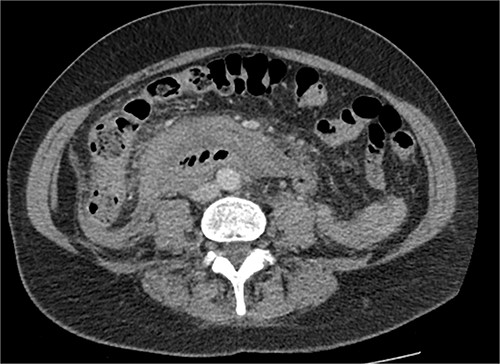

The radiologist suggested a computer tomography (CT) scan to further explore the potential causes for this fluid. The CT abdomen and pelvis revealed extensive oedema and induration surrounding the duodenum with a complex hyperdense fluid, extending from this site to the paracolic gutters and into the pelvis. While these findings are suspicious of a paraduodenal hemorrhage from a ruptured duodenal ulcer and hemoperitoneum, they were not typical for perforated duodenal ulcer or erosion into the blood vessels. Differentials were an infiltrating mass either fibrotic or of a lymphoproliferative origin. However, this could not explain the complex fluid in the abdomen (Figs 1 and 2).

CT abdomen, axial view. Hyperdense fluid centered around the duodenum and tracking into the paracolic gutters. Appearance concerning for paraduodenal hemorrhage, infiltrating mass was considered less likely.